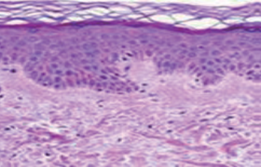

3. 월경진 피부조직

정상피부

신경섬유종